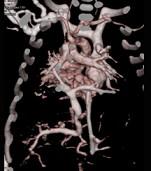

问题 女性,21岁,活动后呼吸困难,时常发生上呼吸道感染,CT扫描如图所示,请选择正确的选项 ( )

选项 A、该病人肺静脉异位引流入下腔静脉 B、该病人为心下型肺静脉异位引流 C、肺静脉异位引流根据引流肺静脉支数的不同可分为部分性及完全性 D、根据引流部位不同分为心上型、心脏型、心下型 E、考虑为肺静脉异位引流

答案 ABCDE